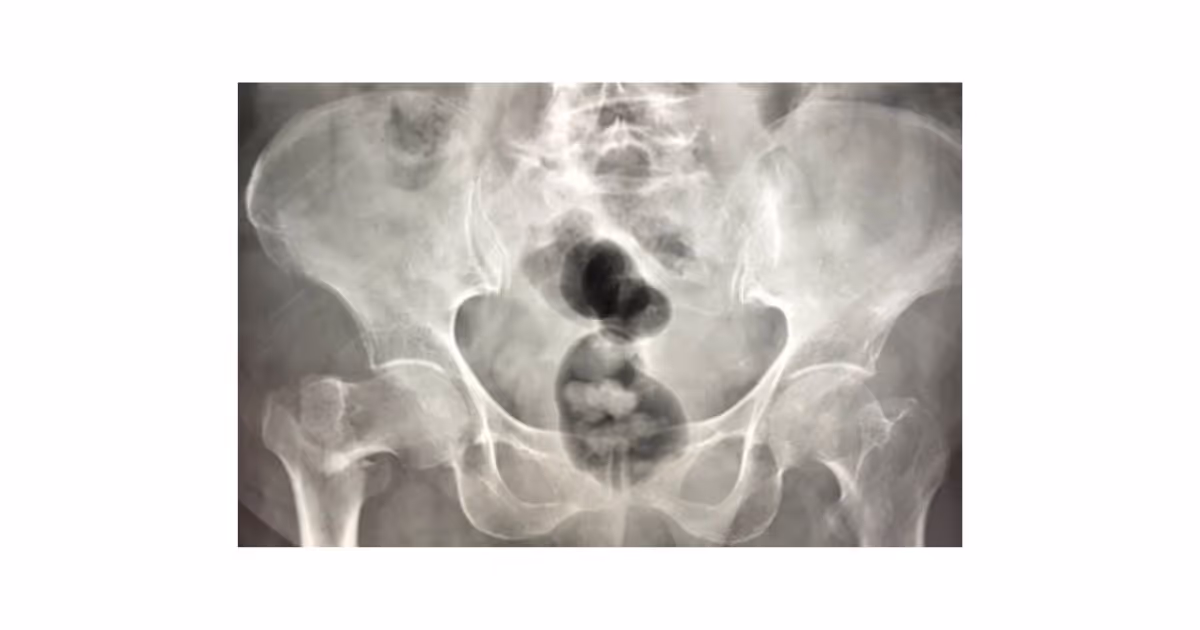

อาการที่ควรจะสงสัยและพามาพบแพทย์ ได้แก่ อาการปวดบริเวณรอบสะโพก ไม่สามารถขยับ หรือลงน้ำหนักที่ขาข้างนั้น ขาข้างที่เจ็บอาจจะดูสั้นกว่าอีกข้าง  นอกจากนี้ในรายที่เป็นกระดูกหักแบบไม่มีการเลื่อน อาการปวดจะไม่มาก และอาจลงน้ำหนักเดินได้ แต่หากปล่อยทิ้งไว้โดยไม่ได้รับการรักษาจะทำให้อาการบาดเจ็บเป็นมากขึ้นได้ จึงควรมาพบแพทย์เพื่อตรวจเพิ่มเติม โดยแพทย์จะทำการซักประวัติ ตรวจร่างกาย และทำการ X ray เพื่อยืนยันการวินิจฉัย

ภาพ X-ray แสดงการหักของกระดูกสะโพกข้างขวา